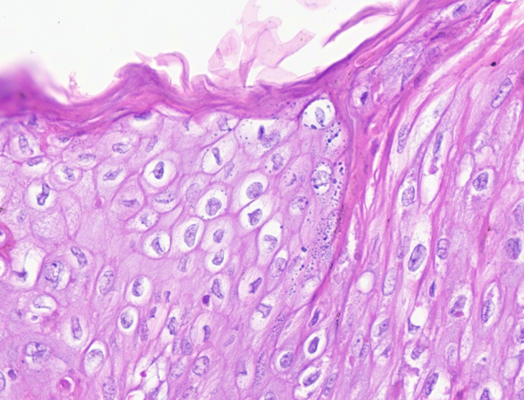

What is the pathogenesis of papillomaviruses?

Infects basal layer of keratinocytes only

Replicated only in well differentiated keratinocytes

Usually increase proliferation of keratinocytes

Define papilloma

1-2 cm wart-like, filiform (long, thin, hair-like), exophytic (raised), and hyperkeratotic mass composed of hyperplastic epidermis supported by dermal stalks

What can papillomaviruses induce?

Other types of neoplasms as viral plaques

In situ carcinoma

Squamous cell carcinoma

What is the difference between viral and non viral papillomas?

Viral

Younger animal

Mass can wane away, stay stable or progresses to squamous cell carcinoma

Presence of koilocytes = abnormal squamous ep. cells, enlarged nucleus (cytopathic effect)

Non viral

Older animals

Mass remains stable usually

Absence of koilocytes